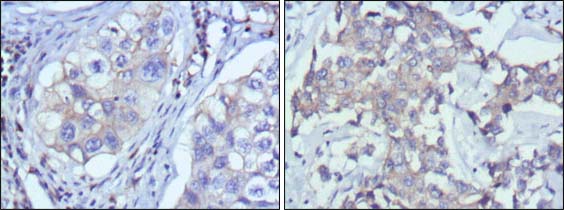

分类: 科研抗体货号: 20343别名: CMH8; VLC1; MLC1V; MLC1SB应用: WB,IHC反应种属: Human

分类: 科研抗体货号: 20377别名: TRKC; gp145(trkC)应用: WB,IHC反应种属: Human